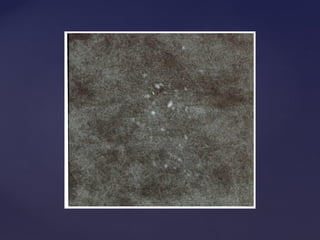

Descrição dos achadosDescrição dos achados

Calcificações

1.Morfologia das partículas

2.Distribuição do agrupamento

Puntiforme Redonda Anelar Em bastão Grosseiras heterogêneas Pleomórficas finas Amorfas tênues Lineares

Agrupadas Lineares Segmentares Regionais Esparsas

Distorção focal de arquitetura